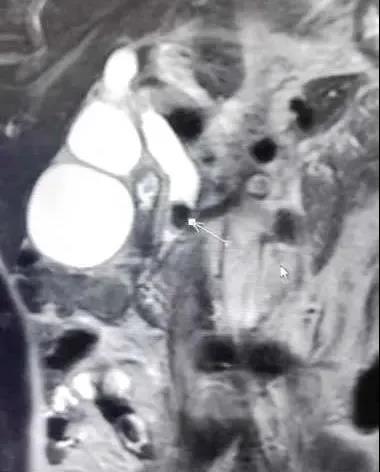

▲MRCP图片

患者女性,53岁,因“持续性上腹部疼痛不适3天”为主诉入住普外科,入院后,科室主任张永全立即召集全科医师对患者进行详细检查,并对病情进行了分析讨论,最终诊断为:胆囊结石伴急性胆囊炎、胆总管扩张。考虑到胆总管扩张原因较多,为进一步明确诊断,在得到患者及家属同意后,决定由张主任主刀,李金科副主任医师、徐亚文主治医师、崔仁杰住院医师协助在全麻下为患者行胆囊切除术+胆道镜下胆总管探查术,手术过程顺利,患者术后安返病房,目前恢复良好。

胆总管扩张原因

胆总管结石、胆管肿瘤、胰头癌、急慢性胰腺炎、胆道蛔虫、先天性胆总管囊状扩张,oddi氏括约肌狭窄、胆囊切除术后代偿性扩张、老年性生理扩张、先天因素等。